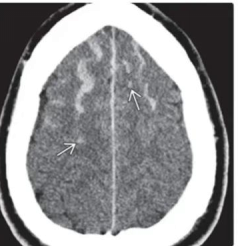

图片说明:男,26Y,外伤后,皮质下多发出血灶(白色箭头所示),蛛网膜下腔出血

大脑灰白质交界处、胼胝体、脑干等好发部位出现微小的点状出血(<1-2毫米)。

脑组织弥漫性肿胀(脑室、脑池受压变窄)。